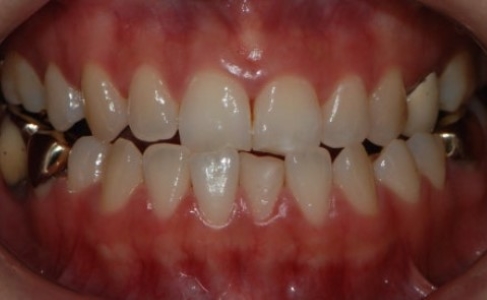

케이스 1. 앞니·어금니가 모두 거꾸로 물렸던 주걱턱, 수술 없이 교정으로

먼저, 비수술 교정으로 치료를 잘 마친 환자분의 치료 전 상태를 보겠습니다.

원칙적으로 이상적인 앞니 교합은

윗니가 아랫니보다 살짝 앞으로 나와

아랫니를 부드럽게 덮어주는 형태입니다.

어금니 역시

윗니가 아랫니보다 약간 바깥쪽에 위치하면서

아랫니를 안정적으로 감싸는 모습이 이상적입니다.

하지만 이 환자분의 경우에는,

앞니와 어금니가 모두 거꾸로 물리는 반대교합 상태였습니다.